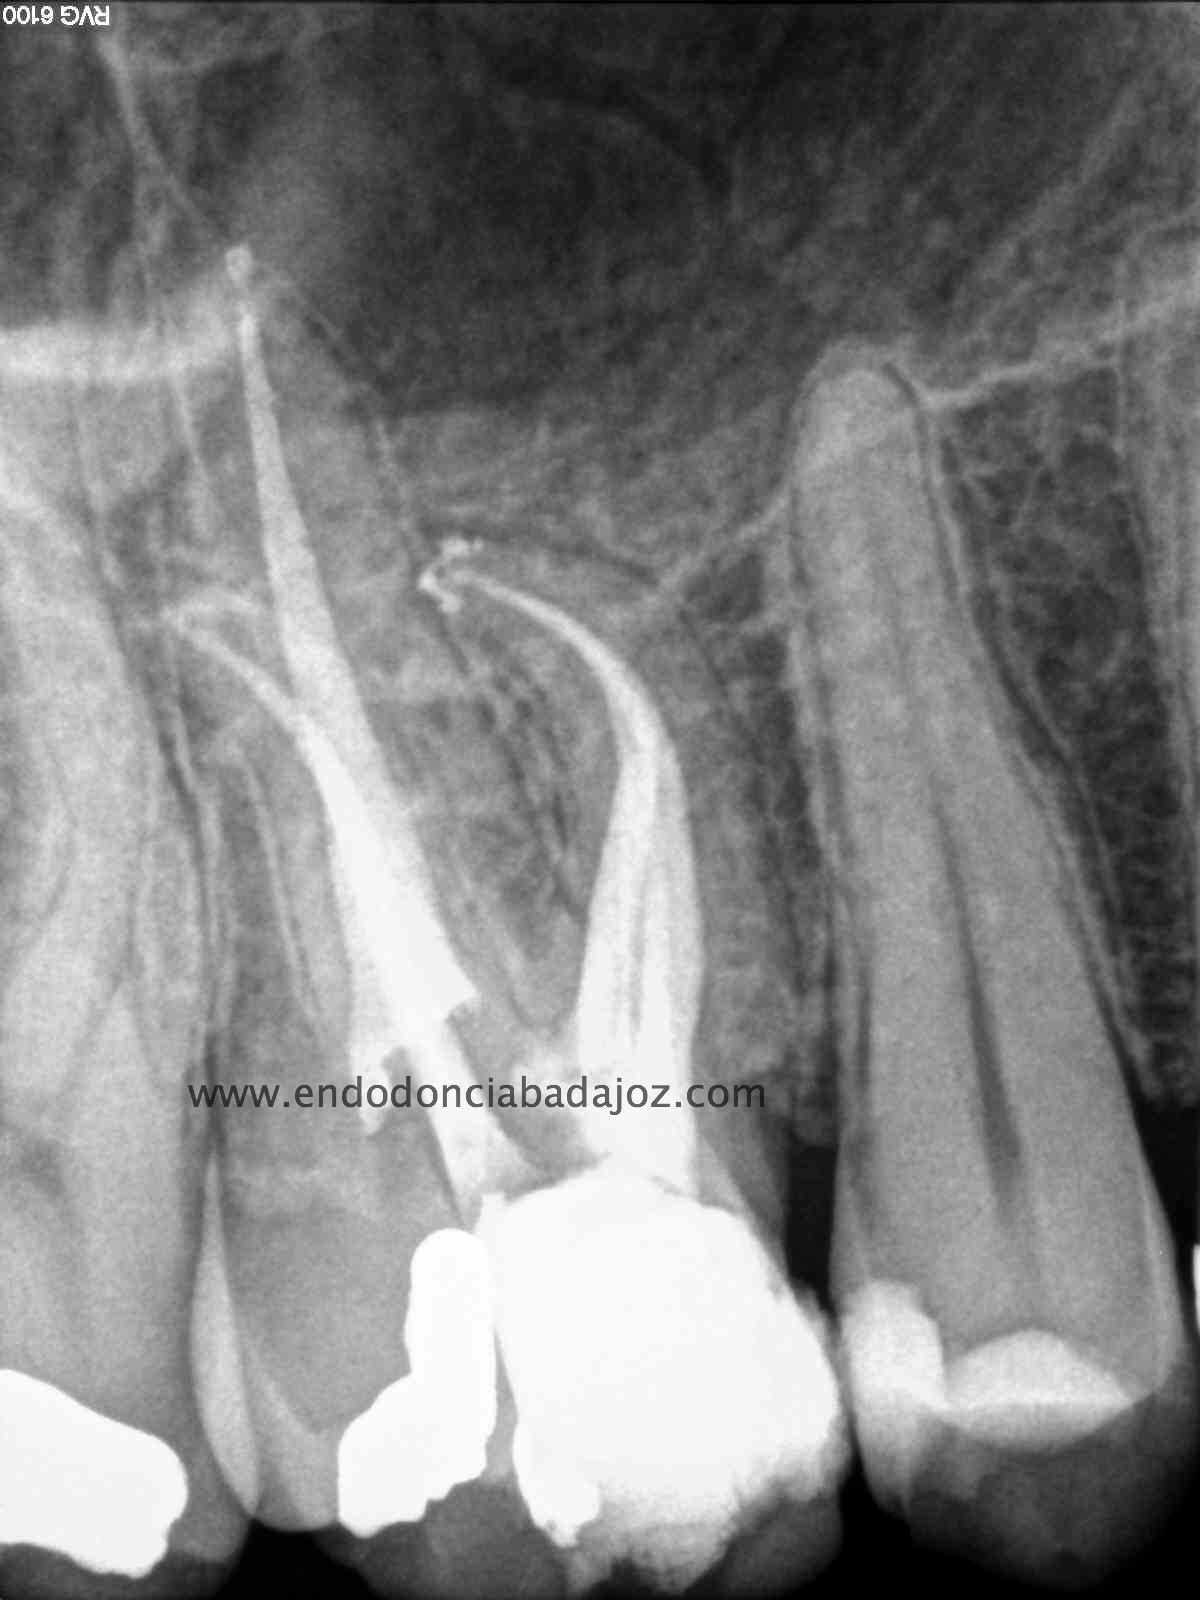

( Otra molar superior con 3 conductos mesiales)

Esta última foto corresponde con un caso de un primer molar superior que la Rx no me esperaba que tuvieses tres conductos mesiales:

Son casos complicados, este en particular, por la ligera curva apical, que se agrava con la curva coronal, con lo que debemos  aliviar modificando la apertura y acceso del tercio coronal con ultrasonidos e instrumentación.

Usamos los sistemas Pathfiles y las Mtwo, consiguiendo una buena preparación  de los conductos